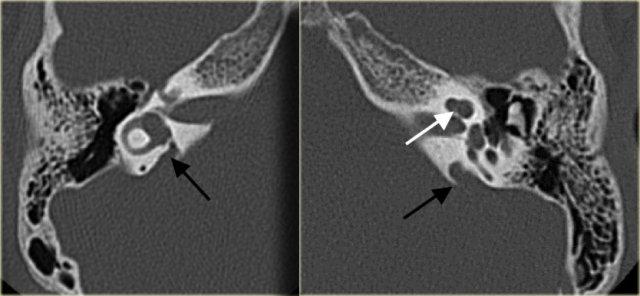

Cống tiền đình giãn rộng hai bên (mũi tên đen). Trụ ốc tai xương không quan sát thấy (mũi tên trắng).

Cống tiền đình giãn rộng

Cống tiền đình là một ống xương hẹp (cống) nối túi nội dịch với tai trong (tiền đình).

Chạy qua ống xương này là một ống gọi là ống nội dịch.

Cống tiền đình giãn rộng có liên quan đến tình trạng nghe kém tiếp âm tiến triển.

Sự tiến triển này được cho là có liên quan đến chấn thương đầu nhẹ, làm tai trong tiếp xúc với sóng áp lực qua cống tiền đình giãn rộng.

Cống tiền đình giãn rộng có liên quan đến sự vắng mặt của trụ ốc tai xương ở hơn 90% bệnh nhân.

Bên trái là hình ảnh của một bệnh nhân có cống tiền đình giãn rộng hai bên.

Lưu ý rằng trụ ốc tai xương không quan sát thấy.

Bên trái là hình ảnh của một bé trai 5 tuổi với tình trạng nghe kém tiến triển hai bên.

Quan sát thấy cống tiền đình giãn rộng (mũi tên đen).

Ốc tai không có trụ ốc tai xương (mũi tên trắng).